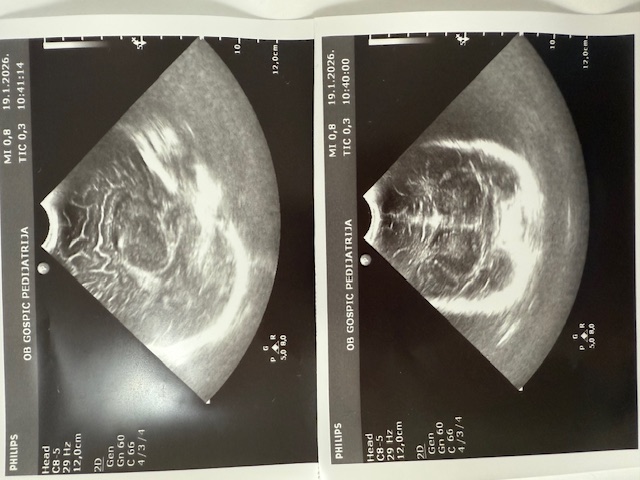

Posebnu vrijednost Dječjeg odjela predstavlja Ultrazvučna ambulanta u kojoj se već punih 20 godina provodi jedinstveni dojenački probir na bolesti i razvojne poremećaje mozga te razvojne poremećaje zgloba kuka. Riječ je o jedinom takvom sustavnom probiru u Hrvatskoj, koji se provodi po principu skrininga, odnosno usmjeren je na otkrivanje poremećaja kod naizgled zdrave djece. Svako dojenče rođeno u Općoj bolnici Gospić obavlja oba pregleda kao standardni dio zdravstvene skrbi.

Probir provodi pedijatrica i ravnateljica bolnice dr. Sandra Čubelić, a analiza pokazuje da se godišnje obavi oko 1200 ultrazvučnih pregleda. U proteklih 20 godina provedeno je približno 25 tisuća pregleda, što ovaj program svrstava među najznačajnije dugoročne zdravstvene nadstandarde u regiji. Iako su se pregledi u početku obavljali u novorođenačkoj dobi, danas je uobičajeno da se provode kada dojenče navrši mjesec dana.

Svrha probira je rano otkrivanje poremećaja, prije nego se pojave simptomi ili znakovi bolesti. Upravo zahvaljujući tom pristupu, kod dvoje djece pravodobno je izvedena operacija mozga prije nego što su se razvile bilo kakve smetnje psihomotornog razvoja. Blaži razvojni poremećaji otkrivaju se znatno češće, što omogućuje pravodobno praćenje i liječenje. Kod zgloba kuka razvojni poremećaji se razlikuju po težini – luksacije i subluksacije javljaju se rjeđe, dok su displazije češće. Cilj pregleda je započeti liječenje prije nego dijete prohoda, jer se poremećaji otkriveni kasnije liječe teže, dugotrajnije i nerijetko operativnim zahvatima.